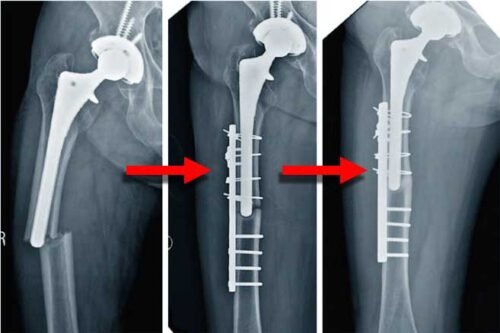

6. كسور عظمة الفخذ

قد يحدث الكسر أثناء الجراحة ولا سيما نتيجة الدق على المفصل الصناعي اثناء تركيب المفصل الغير أسمنتي في عظمة الفخذ.

و لكن اغلب الكسور تحدث نتيجة إصابات بعد فترة طويلة من الجراحة مثل السقوط و حوادث السيارات. ويمكنكم الإطلاع على تفاصيل كسور العظام بعد تركيب المفاصل الصناعية بالنقر هنا.

الأعراض

- ألم حول الورك أو الفخذ

- عدم القدرة على تحمل الوزن

- تبدو الساق المصابة أقصر واستدارة

- تورم وكدمات حول الورك

و علاج هذه الكسور يتوقف على مدى ثبات المفصل في العظام بعد الكسر وعلى موضع الكسر في العظام ومدى وجود هشاشة في العظام. ويتم علاج هذه الحالات عن طريق:

- استخدام شرائح ومسامير: حيث يتم رد العظام المكسورة الى موضعها الأصلي وتثبيتها باستخدا شريحة ومسامير وربما بعض الاسلاك التي يتم لفها حول عظمة الفخذ. و قد يتم الاستعانة بعمل ترقيع عظمي في بعض هذه الحالات.

- اذا كان المفصل غير ثابت في العظام فيتم إستبداله وتركيب جزء جديد بدلا منه أثناء الجراحة. و غالبا يكون الجزء الجديد أطول ليقوم بتثبيت الكسر.